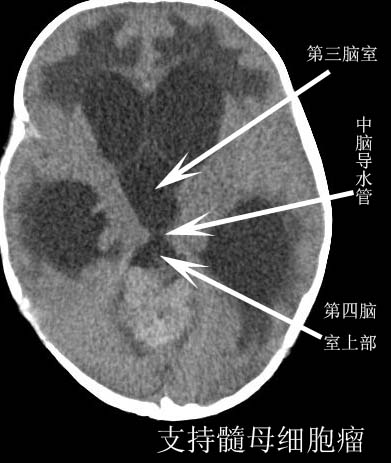

以下是引用卜一在2008-9-10 16:21:00的发言:[br]髓母细胞瘤伴梗阻性脑积水!支持![br]髓母细胞瘤特点:—般直径大于3.5cm,位于后颅凹中线之小脑蚓部。累及上蚓部的肿瘤延伸到小脑幕切迹之上,ct平扫肿瘤多呈均匀一致的高或等密度病灶,增强检查呈均匀一致的强化。病灶中有小坏死时,平扫亦可呈不均匀之混杂密度,注药后有增强。[br]

以下是引用zjzjr在2008-9-10 15:09:00的发言:[br]髓母细胞瘤伴梗阻性脑积水.